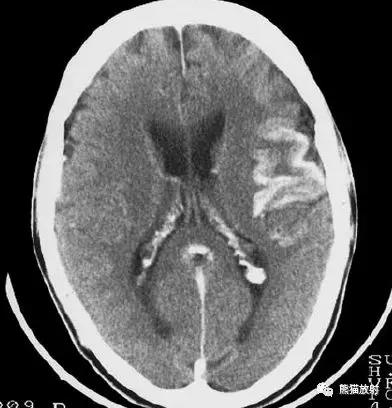

左侧大脑中动脉区域大面积梗死,明显不均质强化。

右侧大脑中动脉区域脑梗死,脑回样强化。

左侧额叶脑梗死(发病后12d),由于模糊效应平扫显示不清,增强扫描脑回样强化。

右侧基底节区脑梗死,增强后病灶看上去有所缩小。